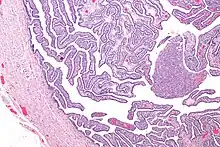

Micrograph of salpingitis – a component of pelvic inflammatory disease. H&E stain.

Upon a pelvic examination, cervical motion, uterine, or adnexal tenderness will be experienced.[5] Mucopurulent cervicitis and or urethritis may be observed. In severe cases more testing may be required such as laparoscopy, intra-abdominal bacteria sampling and culturing, or tissue biopsy.[15][23]